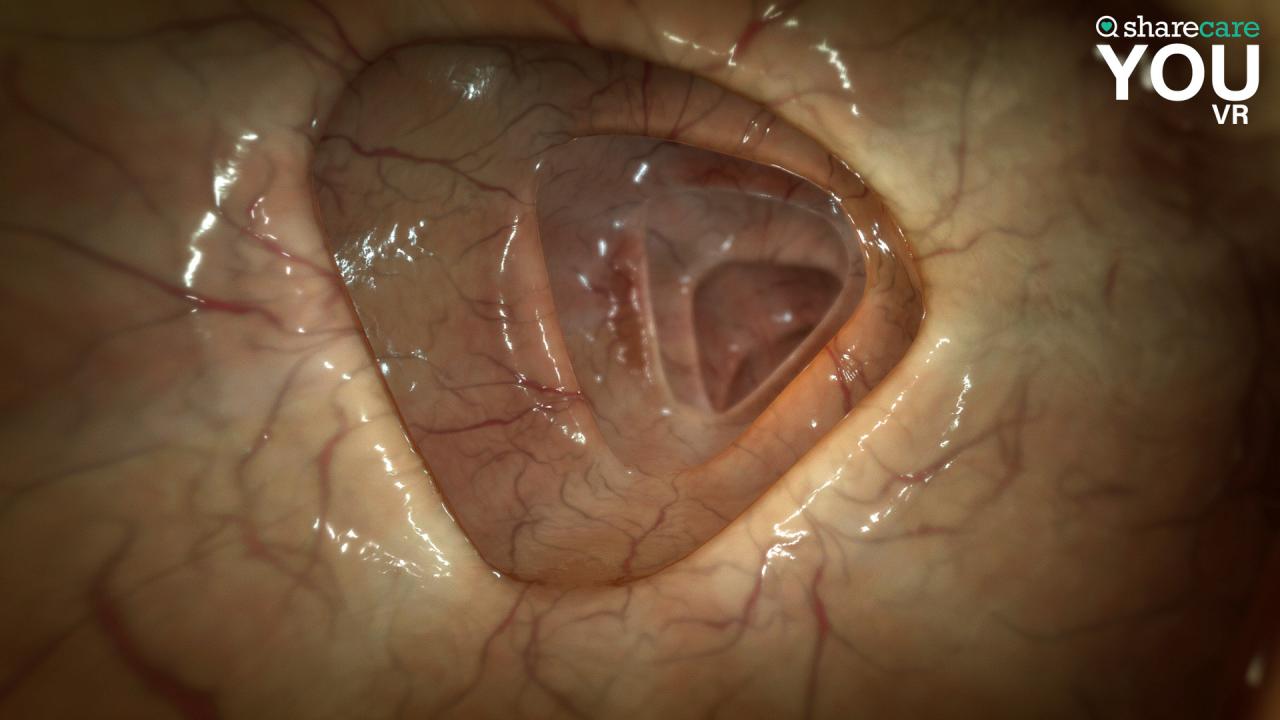

Испытайте человеческое тело, как никогда раньше! Sharecare YOU VR предоставляет вам невиданный опыт в человеческом теле, который позволяет лучше визуализировать, понимать и взаимодействовать с человеческим телом. Sharecare YOU VR - это не скучное приложение для анатомии или простая демонстрация 2D-видео, это полностью захватывающий и интерактивный опыт 360, который вы должны попробовать для себя! Тысячи структур и систем органов для изучения растущей библиотеки контента и видео, включая анатомию, физиологию, условия и методы лечения Информативные ярлыки и контекстную информацию с закадровым произношением Обновленные интерактивные инструменты и функциональность для анализа, обработки, настройки и изучения каждого органа в 360 градусов Совместимость со всеми основными VR-гарнитурами